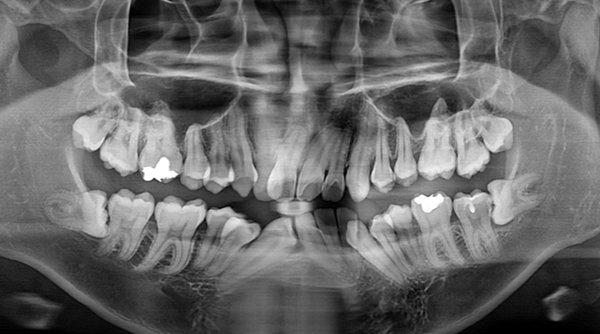

교정치료 중 필요한 사랑니 발치

After

교정 치료와 동반하여 매복 사랑니를 발치한 케이스 입니다.

때로는 교정 치료를 위해서 사랑니 발치를 해야하는 케이스도 있습니다.